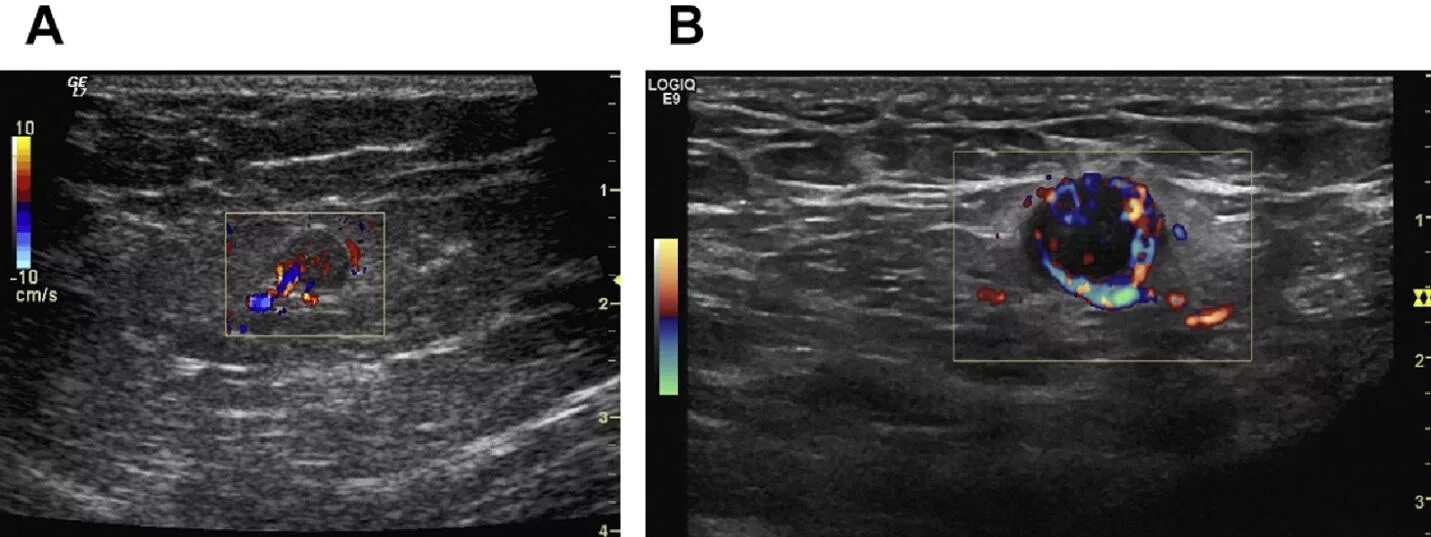

Лучевая терапия метастазов в лимфоузлах